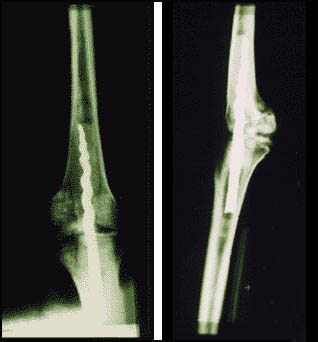

研究期间,他们有了惊人的发现:在Usermontu 的左膝中发现了一根9英寸(23公分)的金属螺丝钉,它连接着大腿和小腿,证明将近2600年前就曾实施先进的外科手术。

科学团队发现古代有机树脂的痕迹,它固定了钉子,可媲美现代的骨水泥(bone cement),他们还发现了古代脂肪和织品的残留物。